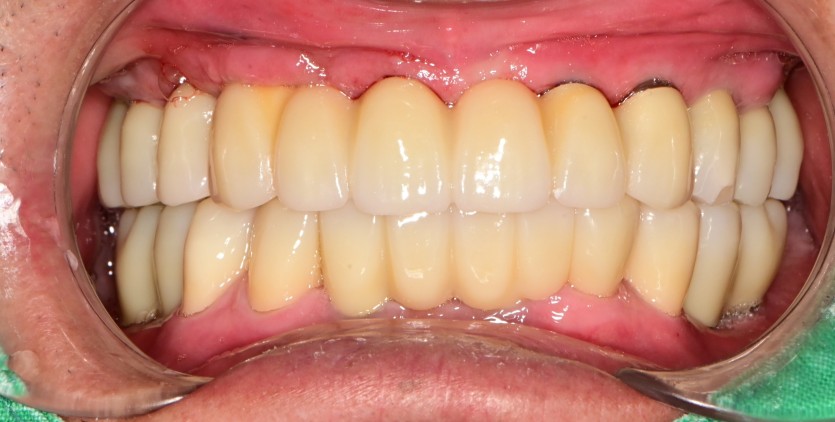

만 66세 전체 임플란트 증례(하악 일부)

전체 임플란트 증례입니다. (하악 일부)

16개의 임플란트로 완성하였습니다.